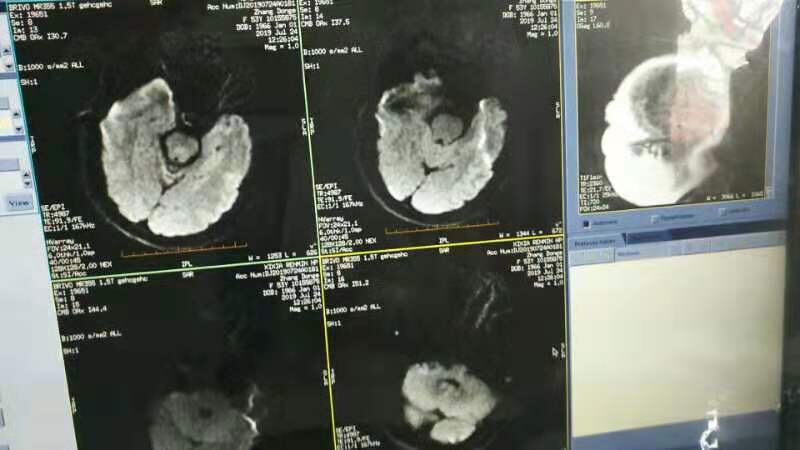

急诊二。zde,f53y。

意识模糊进行性加重8h,基底动脉闭塞,reco取栓再通,貌似动脉硬化,实际血管光滑。造影➕取栓8min。今日团队配合紧密,不到三小时全麻造影取栓带苏醒完成两台取栓。团队棒棒的!南阳市中心医院神经内科脑血管病介入团队